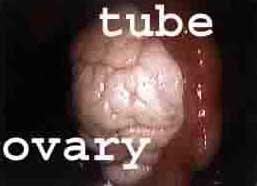

Фиг.1. Нормална тръба и яйцеклетка, както се вижда на лапароскопия